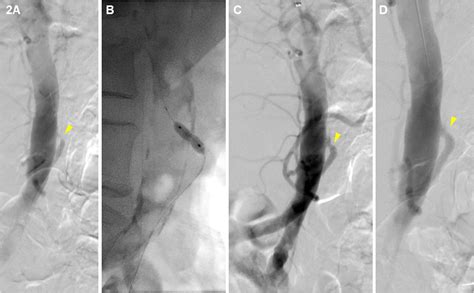

• Angioplasty and Stenting: A minimally invasive procedure where a small balloon is used to open the artery, and a stent is placed to keep it open. This is often the preferred first-line treatment for its shorter recovery time.

• Bypass Surgery: A more traditional open surgical approach where a graft (a synthetic tube or a vein from the body) is used to redirect blood flow around the blocked segment of the artery.